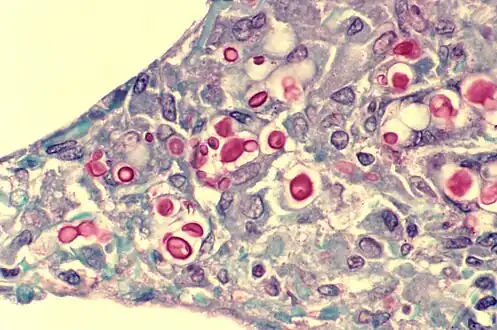

Cryptococcosis of lung in patient with AIDS. Mucicarmine stain. Histopathology of lung shows widened alveolar septum containing a few inflammatory cells and numerous yeasts of Cryptococcus neoformans. The inner layer of the yeast capsule stain red.

A histologic slide of a human alveolar sac

There are three major types of alveolar cell. Two types are pneumocytes or pneumonocytes known as type I and type II cells found in the alveolar wall, and a large phagocytic cell known as an alveolar macrophage that moves about in the lumens of the alveoli, and in the connective tissue between them. Type I cells, also called type I pneumocytes, or type I alveolar cells, are squamous, thin and flat and form the structure of the alveoli. Type II cells, also called type II pneumocytes or type II alveolar cells, release pulmonary surfactant to lower surface tension, and can also differentiate to replace damaged type I cells.[12][15]